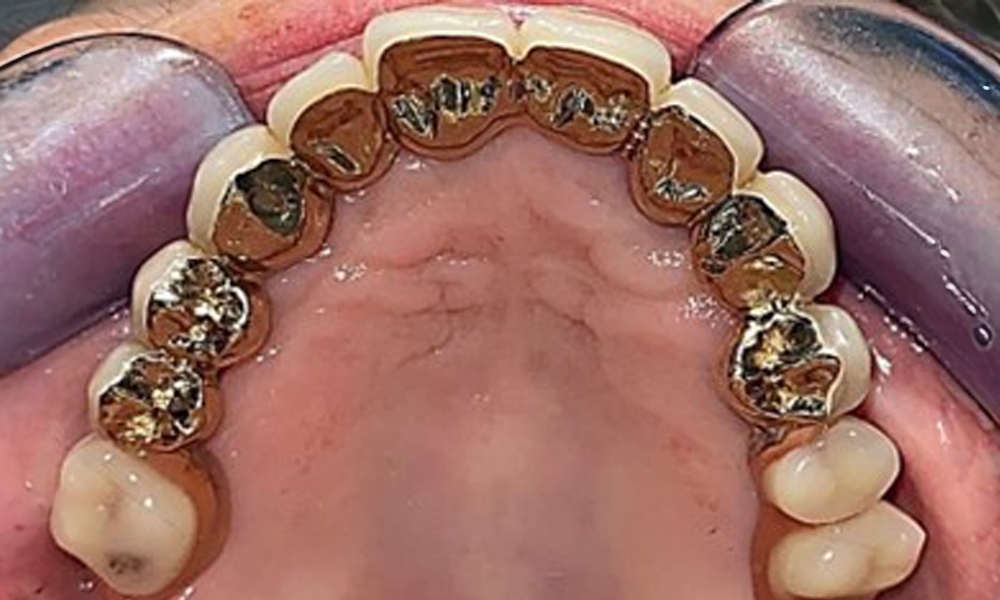

Occlusal view: Maxilla with removable, palateless denture.

Fig. 3: Occlusal view: Maxilla with removable, palateless denture.